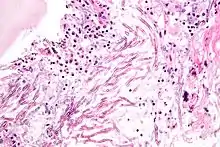

Candida species cause infections in individuals with deficient immune systems. Candida species tend to be the culprit of most fungal infections and can cause both systemic and superficial infection.[6] Th1-type cell-mediated immunity (CMI) is required for clearance of a fungal infection. Candida albicans is a kind of diploid yeast that commonly occurs among the human gut microflora. C. albicans is an opportunistic pathogen in humans. Abnormal over-growth of this fungus can occur, particularly in immunocompromised individuals.[7] C. albicans has a parasexual cycle that appears to be stimulated by environmental stress.[8]